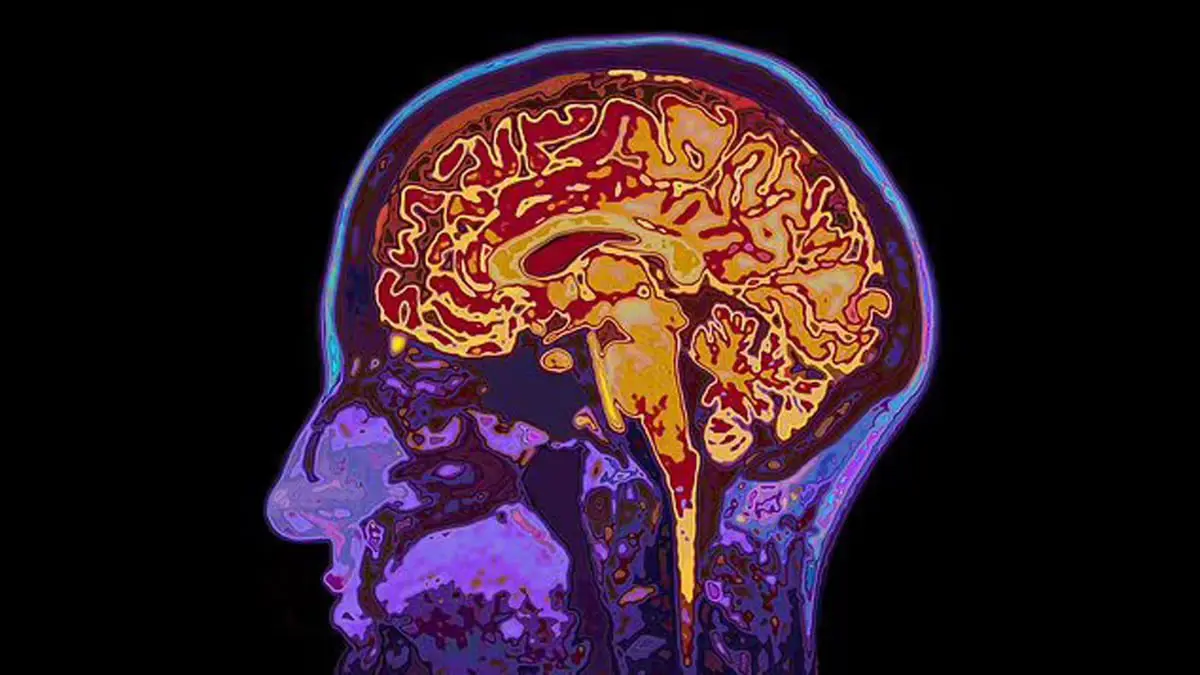

كشف المسح والفحوص عن إصابة جونز بورم في الفص القذالي في المخ، ومن الممكن أن يسبب هذا النوع من الأورام، مشاكل في الرؤية وفقدان الذاكرة أو التفكير الضبابي

ومن المقرر أن يخضع المريض لعملية جراحية لإزالة الورم، لكن هناك احتمالية أن يفقد بصره، حيث أخبره الطبيب المعالج بأن هناك جزءا من الورم يقع في ثنايا الدماغ ما يجعل العملية صعبة بعض الشيء.